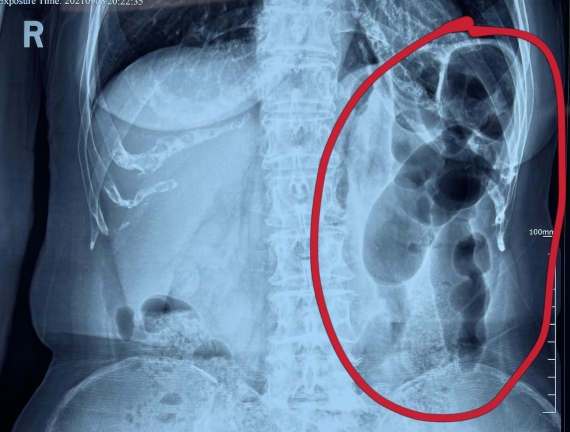

據(jù)省醫(yī)院消化病院消化二科姜子曄醫(yī)生介紹,韓大娘今年已經(jīng)73歲,家住哈爾濱市,一周前開始腹脹腹痛,有較為明顯的左側(cè)腹部疼痛,疼痛劇烈時(shí)會(huì)出現(xiàn)左側(cè)腹部鼓包情況,排氣排便后有所好轉(zhuǎn)。韓大娘家人見狀將其送到了黑龍江省醫(yī)院,門診檢查腹部平片提示為左側(cè)腹部積氣,口服全消化動(dòng)力藥及通便治療后腹痛腹脹有所緩解,入院前再次突發(fā)左側(cè)腹痛加重伴有明顯腹脹,急診隨后以“腹痛腹脹原因待查”將韓大娘收入到消化病院消化二科。

姜子曄醫(yī)生熱情接待了韓大娘,為其進(jìn)行了仔細(xì)查體,除了左側(cè)腹部壓痛并未見明顯異常,對癥給予灌腸后,韓大娘的腹脹有所緩解,第二天姜子曄醫(yī)生為韓女士進(jìn)行了胃腸鏡檢查,也未見明顯異常。但此時(shí)韓大娘腹部平片結(jié)腸腸管擴(kuò)張仍然很嚴(yán)重,腹痛腹痛也沒緩解,到底什么原因呢?消化二科主任陸以霞在查房時(shí)建議繼續(xù)給予韓大娘口服全消化動(dòng)力藥,必要時(shí)灌腸治療,同時(shí)陸以霞主任在追問病史查體時(shí)發(fā)現(xiàn)韓大娘左下腹紅色皮疹和小水泡,反復(fù)抓撓腹部皮膚部分已結(jié)痂,高度懷疑為帶狀皰疹。